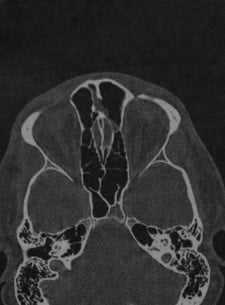

Компьютерная томография височных костей, на которой определяется

распространенное образование верхушки правой пирамиды с тонкими костными стенками.